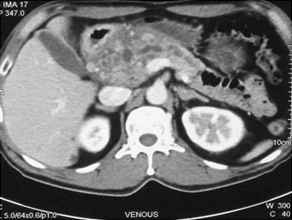

CT scan of pancreatic cancer in the body